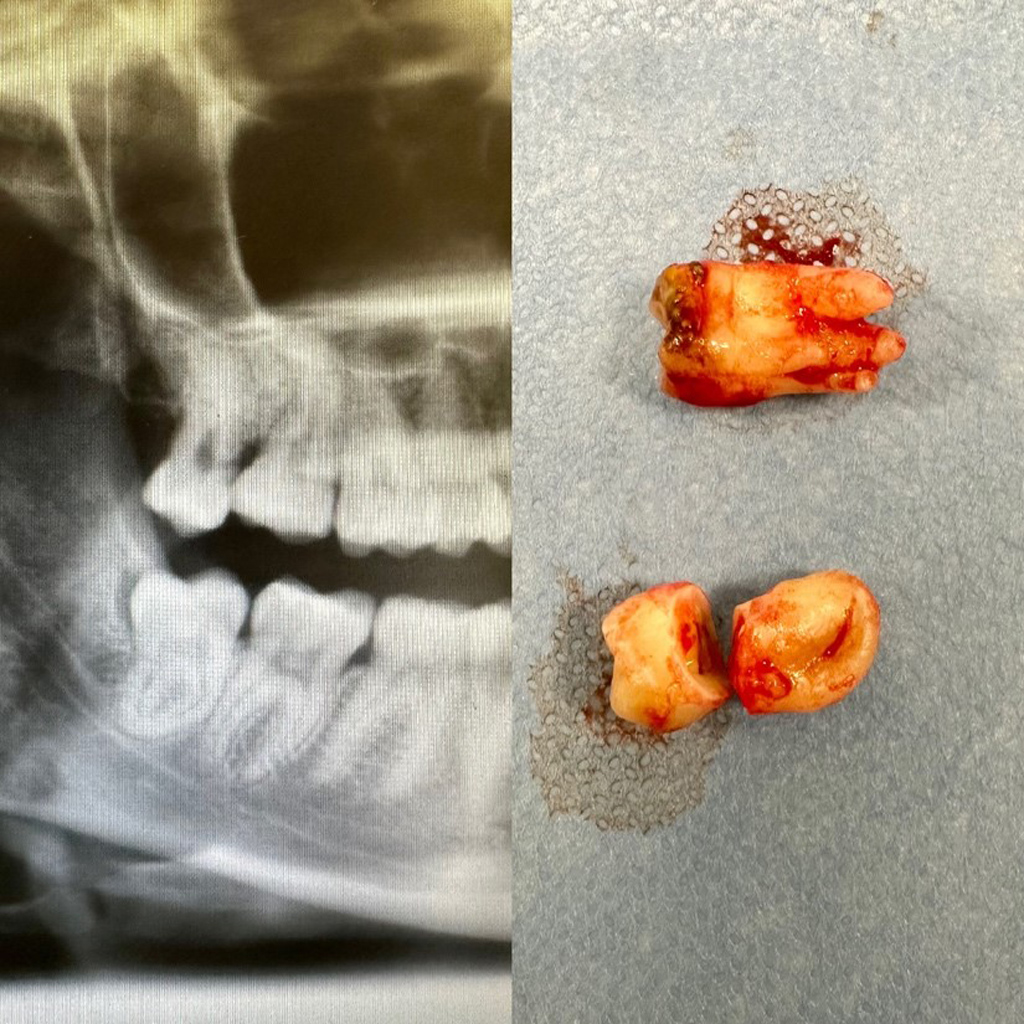

Ekstrakcja zęba mądrości to zabieg chirurgiczny. Trwa 15-30 minut i jest bezbolesny. Diagnostyka zazwyczaj ogranicza się do zdjęcia RTG panoramicznego i niekiedy wymaga wykonania tomografii komputerowej (cbct).

Zdjęcie RTG i usuniętych zębów 18 i 48

zdjecie rtg usunietych zebow 18 48

Chirurgia: dr n.med. Ewa Zawiślak